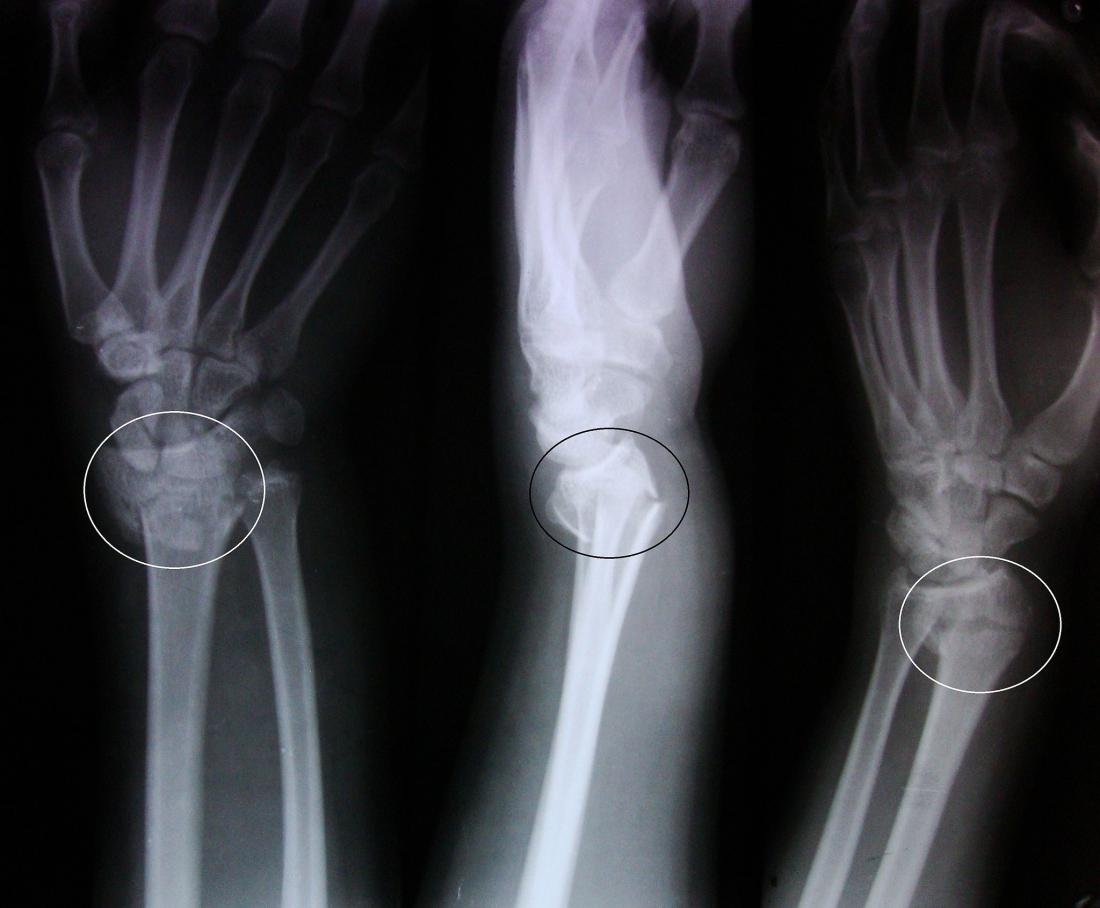

Radiological features of colles fracture: The five commonly seen deformities are:

1. Dorsal angulation with loss of the normal (5-10 degrees) volar tilt of the articular surface of the radius.

2. Dorsal displacement of the distal fracture fragment.

3. Impaction at the fracture site.

4. Radial displacement of the distal fragment.

5. Radial tilt of the distal fragment.